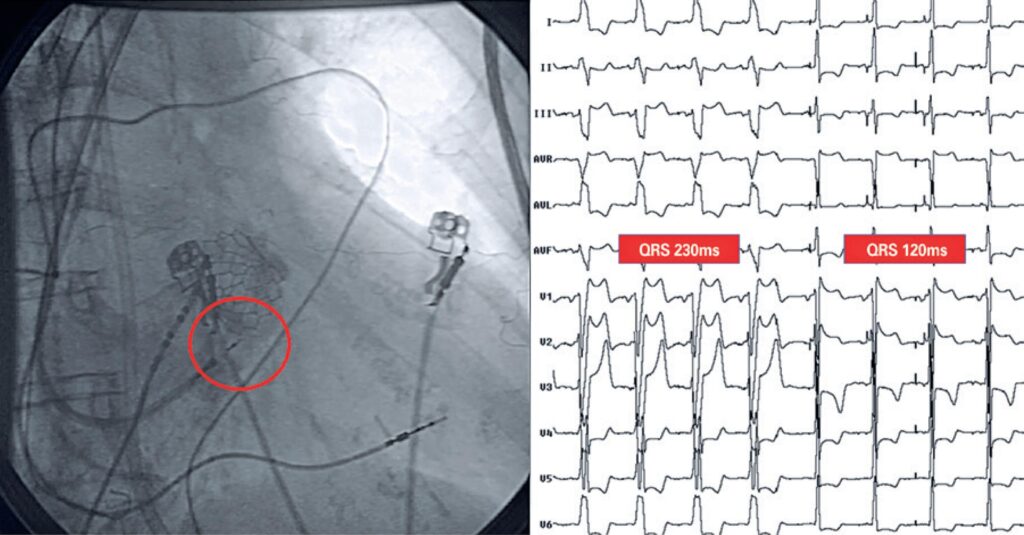

Implante transcateter de valva aórtica e marca-passo em feixe de His na vigência de disfunção ventricular esquerda grave e bloqueio de ramo esquerdo

A estenose aórtica é a doença valvar mais prevalente em países desenvolvidos e apresenta alta morbidade e mortalidade após o início dos sintomas. A prevalência de estenose aórtica grave em pacientes idosos (>75 anos) é de aproximadamente 3,4%. O implante transcateter de valva aórtica tem quase 20 anos de aplicabilidade e resultados robustos publicados. No entanto, é um procedimento desafiador quando realizado em paciente em choque cardiogênico causado por severa deterioração da função do ventrículo esquerdo, situação agravada em casos de dissincronia eletromecânica por bloqueio de ramo esquerdo. Há evidências de que o reestabelecimento da condução elétrica por meio de implante de marca-passo diretamente no sistema de condução em pacientes com disfunção ventricular esquerda e dissincronia pode trazer melhora significativa à função sistólica. Nesse contexto, o objetivo do presente trabalho foi apresentar e discutir as particularidades e as evidências disponíveis para tratamento desse subgrupo complexo de pacientes.